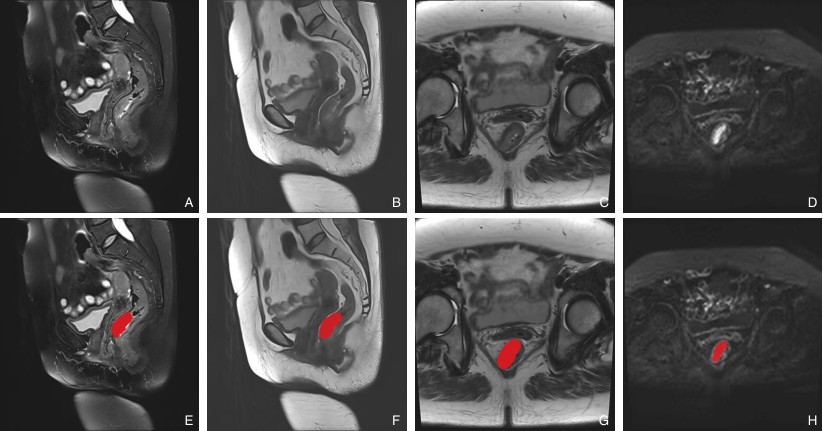

图1 CRC原发灶的多模态MRI图像及相应ROI勾画示意图 A-D:分别为病灶矢状位压脂T2WI、矢状位T2WI、横断位T2WI、DWI图像;E-H:分别为相应ROI勾画示意图Fig.1 Multimodal MRI images of primary CRC lesions and corresponding ROI delineation A-D: Sagittal fat-suppressed T2WI, sagittal T2WI, axial T2WI, and DWI images; E-H: Corresponding ROI delineation